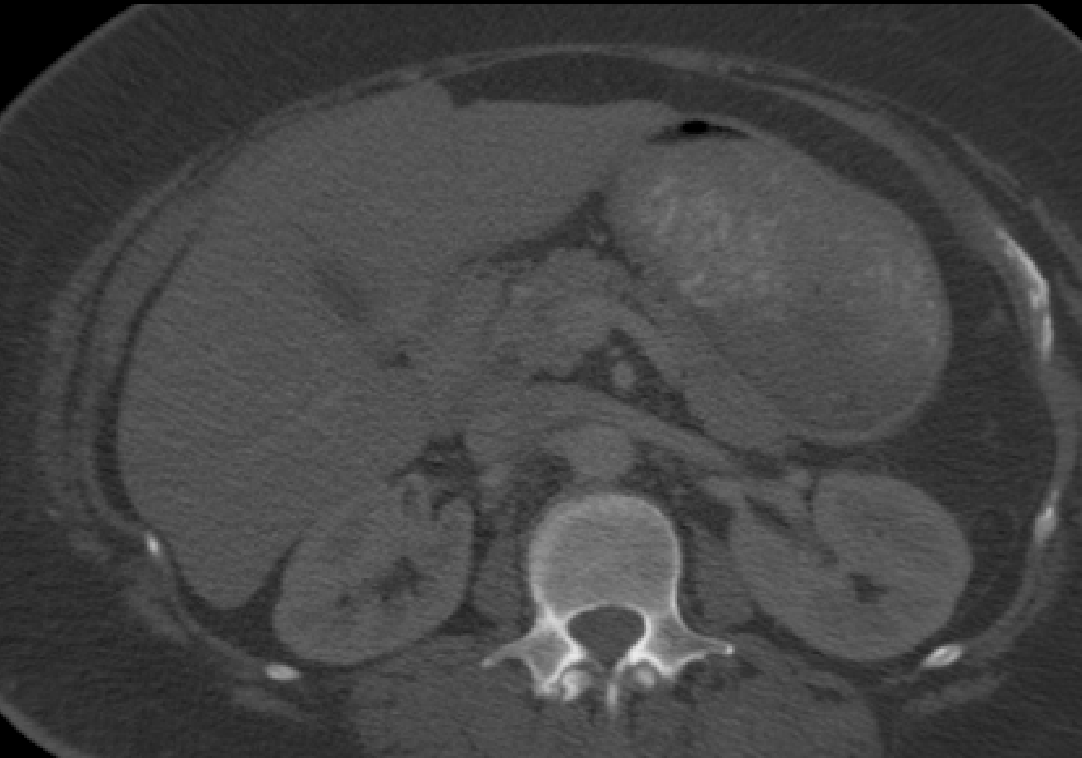

Manual Labels for Verification. We design a mechanism to validate these collected labels by humans. To do so we collect manual labels from 3000 2D image from 300 MRI samples for 10 abdominal organs (UKBOB-manual). These manual labels (see examples in Figure 2) act as a validation for the large UKBOB dataset. On these labels, the UKBOB automatic labels obtain an average Dice Score of 0.891 (see Table 3). Furthermore, we verify the spine labels of UKBOB using previously collected manual labels of 200 3D spine labels [5]. We show an example in Figure 1 and we see how the new collected labels match the manual labels in the spine with a total Dice score of 0.811, indicating accurate labels. We discuss in Section 5.1 another mechanism for verifying the labels by zero-shot generalization of trained models to other similar datasets that has manual labels.

Manual Verification. In Table 3 we validate the quality of the UKBOB labels and the organ quality control against manual spine annotation from [5] and our manually annotated 11 abdomen UKBOB organs (UKBOB-manual). Even without any filtration, UKBOB labels are precise, achieving Dice score of 0.811 and 0.873 on manual spines and UKBOB-manual respectively. We Also show that our SOLF filtering approach (when ) increases Dice score by 0.056 compared to no filtering on the spine labels and by 0.018 on the labelled abdomen organs. We also show standard inter-quartile range filtering (IQR) [30] for comparison.